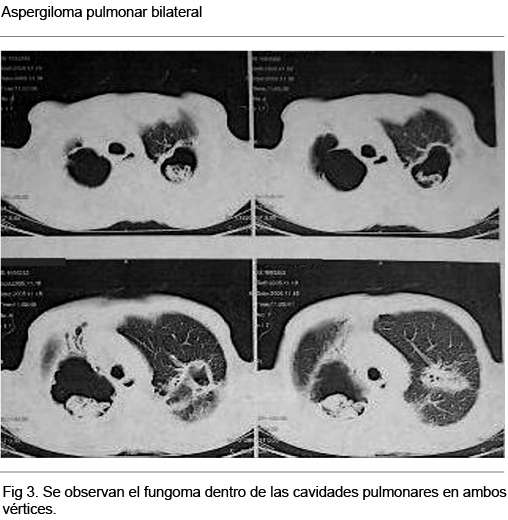

Rx de tórax (Figura 1): importantes elementos secuelares fibro-retráctiles bilaterales a predominio biapical, con cavidades biapicales con nivel hidroaéreo a derecha.

TAC tórax en CTI: en el primer día del episodio rojo (Figura 2): cavidades de LSD y LSI con sangre en su interior; cavidad paravertebral der. con líquido en su interior; masas intracavitarias biapicales.

TAC de Tórax (Control previo al alta de Sala de Medicina): masas micóticas intracavitarias (Figura 3) actualmente se controla en policlínica de Neumología, tratado con itraconazol 400 mg día v/o al alta, en espera para completar los estudios de valoración preoperatorio y optar por una alternativa quirúrgica.